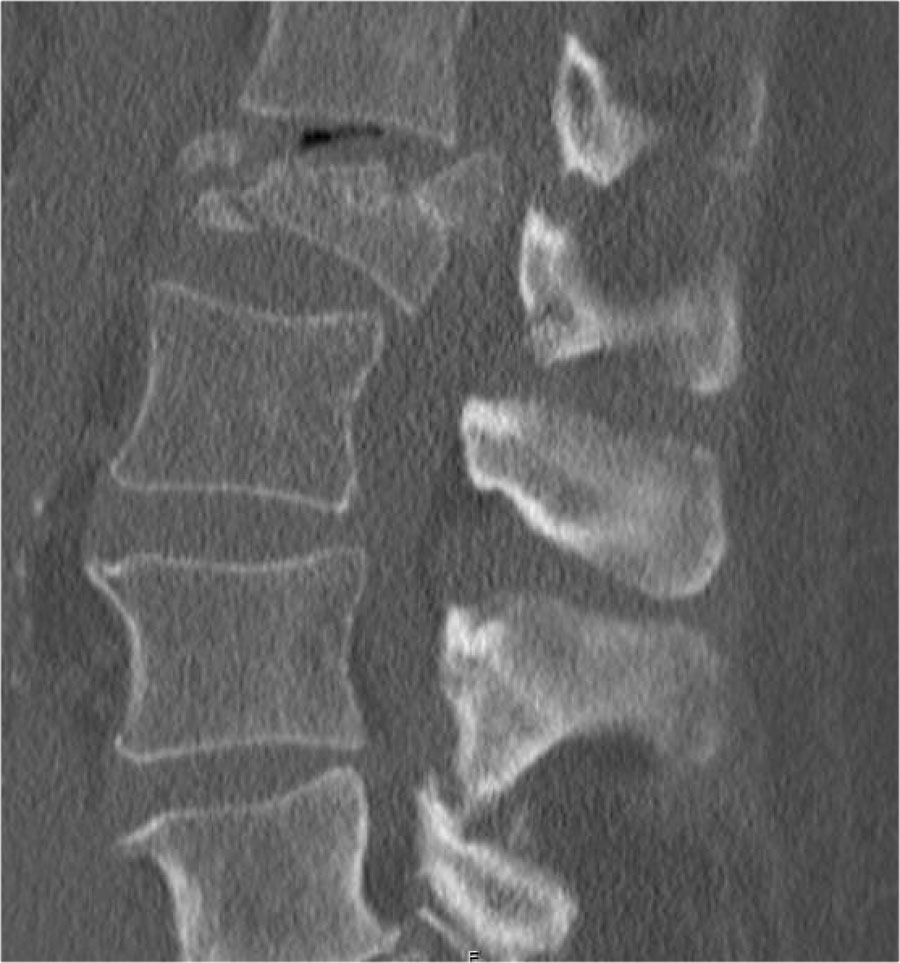

Giãn rộng khoảng cách liên cuống (interpedicular distance)

Giãn rộng khoảng cách liên cuống, thường là hệ quả của đường gãy theo mặt phẳng đứng dọc, gặp trong 80% các trường hợp gãy vỡ.

Hình chiếu bên cho thấy các đặc điểm điển hình của gãy vỡ.

Trên hình chiếu thẳng (AP), lưu ý sự giãn rộng kín đáo của khoảng cách liên cuống so với các tầng trên và dưới.

CT axial và MRI trên cùng một bệnh nhân cho thấy mảnh xương di lệch đang chèn ép vào bao màng cứng (thecal sac).

Trên CT và MRI mặt phẳng đứng dọc, không có dấu hiệu tổn thương dây chằng phía sau.

Dây chằng dọc trước bị đứt.

Khớp mặt bên phải trông hơi giãn rộng trên CT và có dịch trong khớp trên MRI.

Nếu có nhiều dịch trong khớp, chúng ta nên xếp loại là không xác định.

Trong trường hợp này, chúng ta chưa chắc chắn.